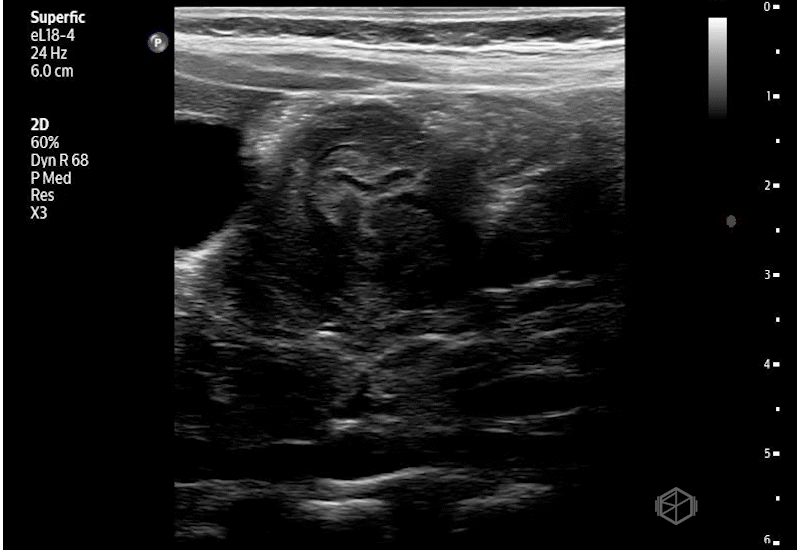

The scan shows echogenic dependent pleural fluid above the diaphragm on the affected side. Fluid layering in a gravity-dependent region (posterior/lateral chest) consistent with pleural effusion in trauma = hemothorax until proven otherwise in a patient with no prior history of pleural effusions. The patient had normal lung sliding bilaterally indicating no pneumothorax. He was found to have 6 rib fractures on CT, but was otherwise stable and pain controlled, saturating well on room air.

Diagnosis: Left hemothorax with multiple rib fractures

• Homogeneously echogenic pleural fluid suggests a hemorrhagic or otherwise complex effusion due to increased cellular/protein content. (📚 PMID: 26218493)

• The presence of internal echoes, swirling debris, or fibrin strands within pleural fluid indicates a complex effusion, which in the trauma setting supports hemothorax rather than simple serous fluid. (📚 PMID: 24626263)

• Clotted blood may produce a layered or heterogeneous appearance, and evolving hemothorax can become increasingly complex over time (PMID: 35984158)